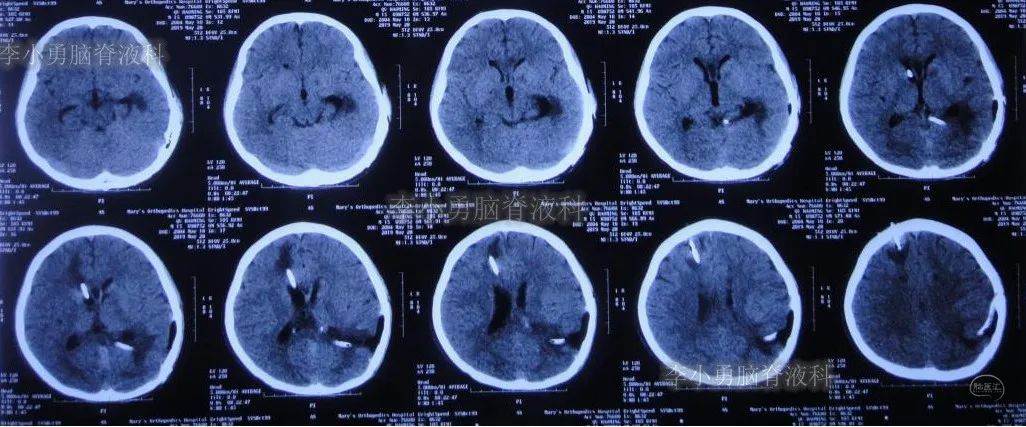

入院当日行头颅CT(图-10):脑室内“动脉瘤切除术”后改变,术区可见引流管影,脑室扩大。

图-10:2019年5月7日头颅CT:引流术后,脑室扩大

入院次日即2019年5月8日,进行了右侧脑室外引流术,并保留原来脑室外引流管(注:脑室内有两根管)。术后常规复查头颅CT(图-11)。

图-11:2019年5月9日头颅CT:引流出淡黄色脑脊液